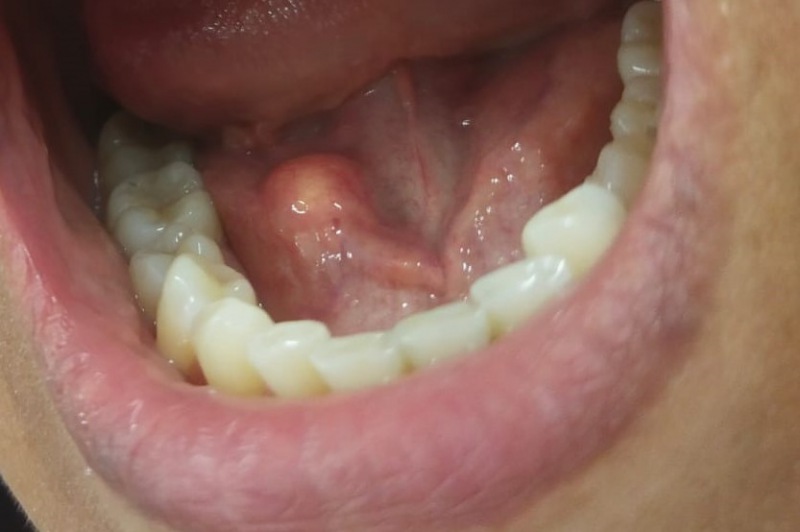

На одной из площадок на консультацию к специалистам Республиканской стоматологической поликлиники обратилась жительница Чебоксар 48 лет. Женщину беспокоили ноющая боль и припухлость в области под нижней челюстью справа, которые появлялись во время еды и проходили самостоятельно через несколько минут.

– При осмотре выявлено увеличение поднижнечелюстной слюнной железы справа, в области выводного протока наблюдалось уплотнение. В срочном порядке пациент была направлена к врачу стоматологу-хирургу.

– При пальпации выявлен слюнный камень. Поставлен диагноз: обструкция (закупорка) протока поднижнечелюстной слюнной железы слюнным камнем.

Конкремент был удален в день обращения, функция железы восстановлена, пациентка вернулась к нормальной жизни.